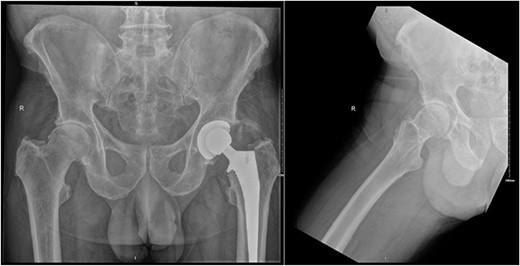

On examination, he had an antalgic gait and his range of motion was globally restricted due to pain. There was significant swelling and erythema over the operative site. His blood investigations demonstrated that his inflammatory markers were mildly elevated: white cell count (WCC) 8.5, CRP 14. X-rays showed satisfactory position of the implants (Fig. 2).

AP pelvis and lateral right hip radiographs 6 weeks post primary right THR when our patient presented with clinical signs of PJI. The implants were in a satisfactory position.